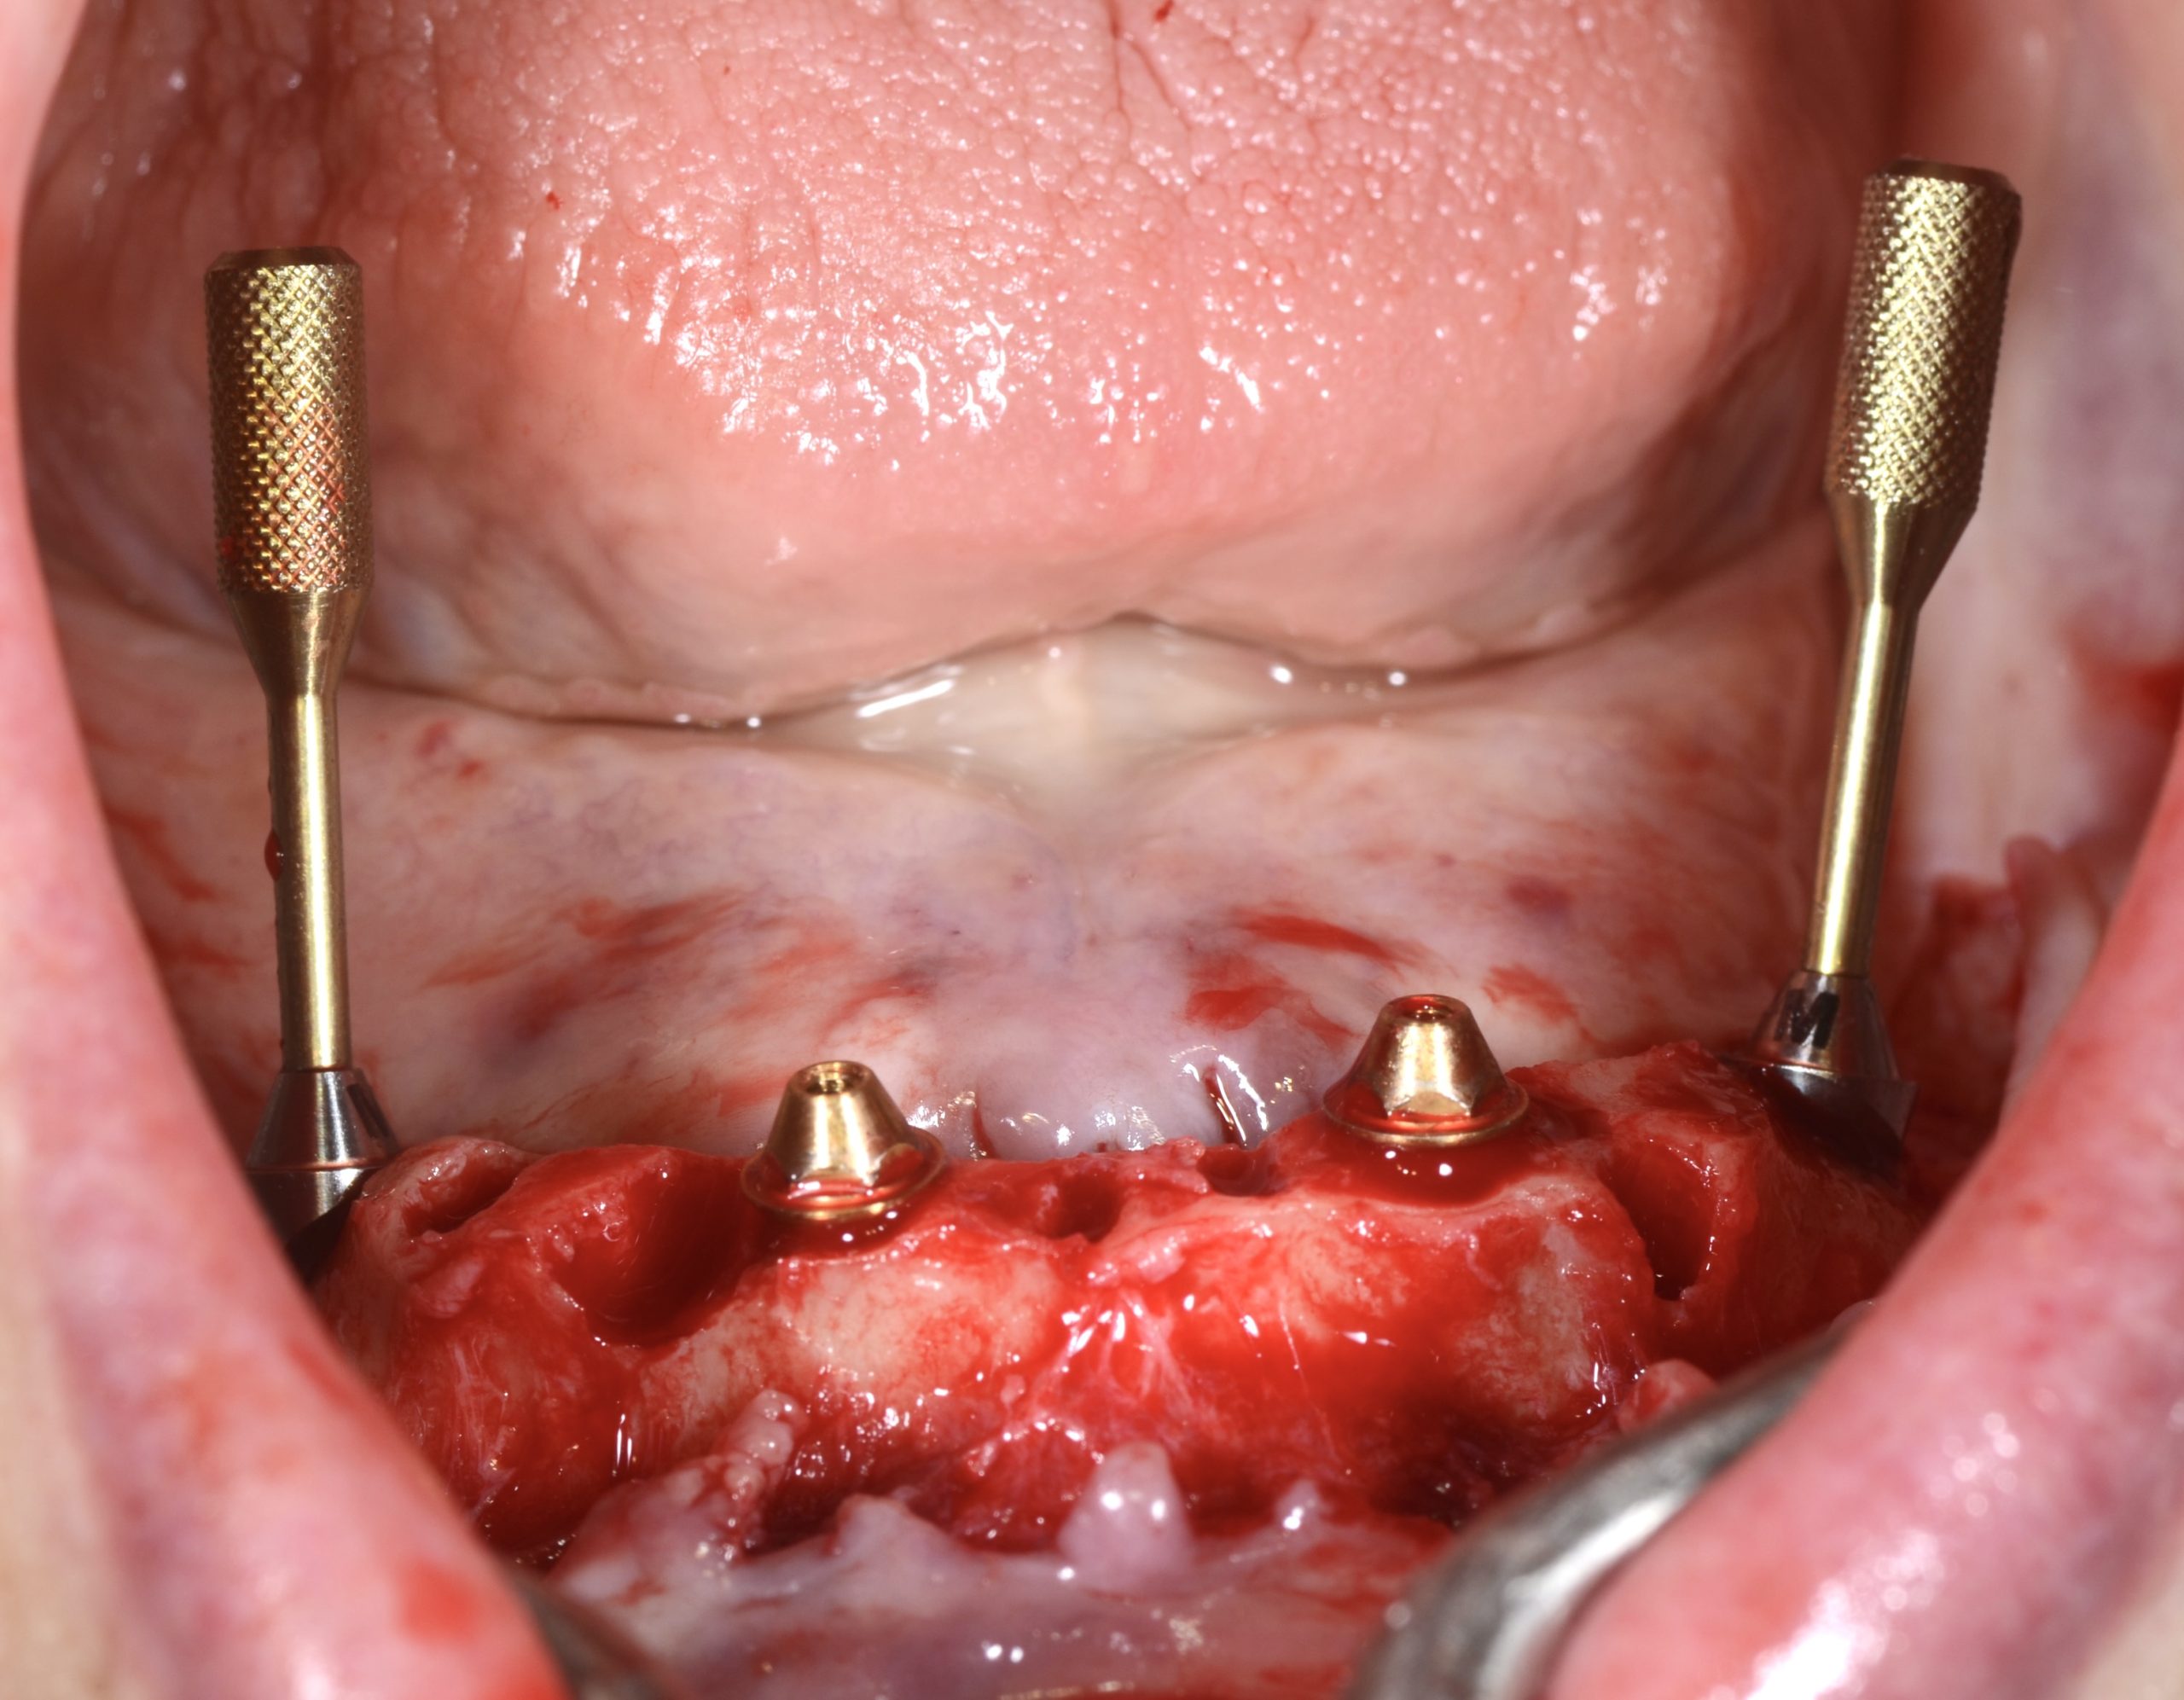

FIG 7